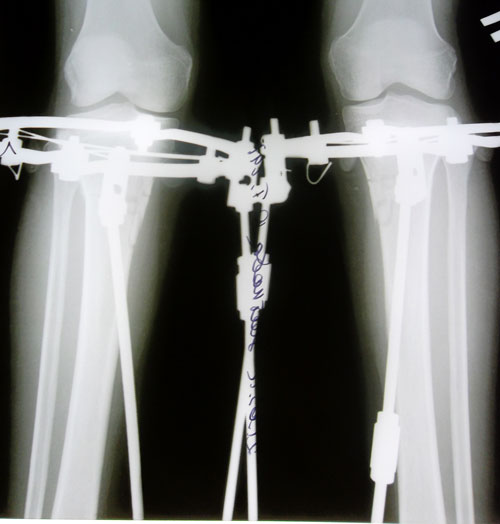

Месяц и неделя после операции, компактные аппаратики Илизарова- Онипко.

Рентген в день снятия аппаратов Илизарова - Онипко.

Результат, аппаратная жизнь 80 дней.